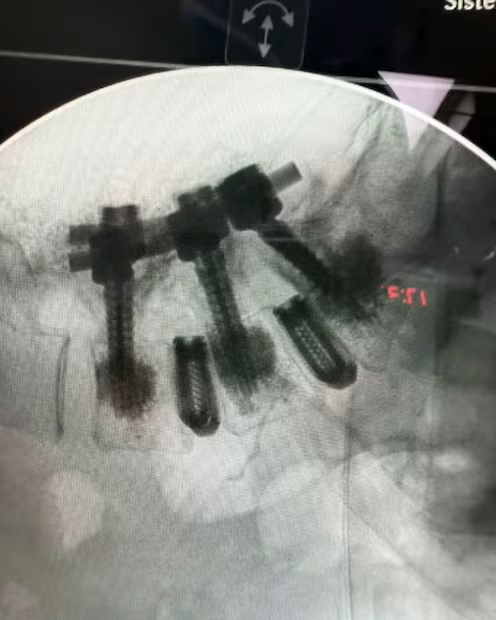

En la foto se ven varios tornillos grandes atr4vesando múltiples vértebras. Estos tornillos se usan para inmovilizar segmentos de la columna.

Se observa una barra metálica que conecta y estabiliza las vértebras donde se colocaron los tornillos. Algunas partes del implante hacen un ángulo, lo que puede indicar corrección de deformidades o estabilización de fracturas complejas. Este tipo de cirugía se realiza en afecciones severas de la columna como fracturas, escoliosis grave, inestabilidad vertebral, o para tratar ciertos tipos de enfermedades degenerativas o tumores.

El objetivo es proporcionar la máxima estabilidad, facilitar la recuperación o evitar daño neurológico adicional. Por la complejidad del implante, parece una cirugía de columna de alta especialización, probablemente en la zona lumbar o torácica (parte baja o media de la espalda).